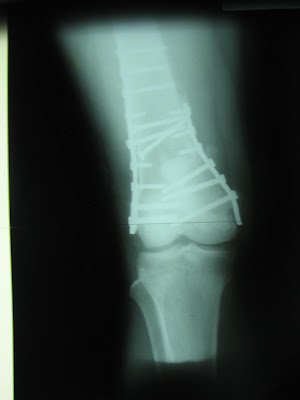

30 yaşındayım. Osteosarkom (kemik tümörü) tanısıyla kimyasal tedavi ve ışın tedavisi gördüm. Kısa bir süre sonra ameliyat olacağım. Nasıl beslenmem gerekir? Tümörün başka organa yayılma riski var mı?

Kemik tümörleri genellikle akciğere metastaz yapar. Ama metastaz yapsa da cerrahi olarak temizlenebilir. 8–10 metastaza kadar cerrahi olarak çıkartılıp tamamen şifa bulan hastalar bile var. Kontrollerinizi düzenli yaptırmayı ihmal etmeyin. Kemik tümörleri kimyasal tedavi ve radyoterapiye çok iyi cevap verir. Hastalar daha sonra cerrahiye yönlendirilir. Hastaların temelli şifa bulma şansı çok yüksek. Kemik tümörlerinde uygulanan kimyasal tedavi ağırdır, bu nedenle proteinli gıdalar almaya özen gösterin. Haftada 2 kez kırmızı et, bol balık, yumurta beyazı, kuru fasulye, bezelye ya da nohut tüketmek protein ihtiyacınızı karşıl ar. Kemoterapi bağışıklık sisteminizi zayıflatır, bu nedenle bütün meyveleri yarım saat sirkeli suda bekletin. Günde 1 gram kalsiyum alabilirsiniz. Doktorunuza danışarak boswellia bitki hapı ve bromelian (ananas hapı)kullanabilirsiniz. Günde 1.5litrenin üzerinde sıvı almaya özen gösterin.Omega3’ten zengin olan semiz otunu çok tüketin.Yüksek doz kemoterapi aldığınız için bağışıklık sisteminiz zayıftır.Bu enfeksiyonlara yatkın olduğunuz anlamına geliyor.Bağışıklık sisteminizi korumak için kemoterapi süresince steril ortamlarda bulunmaya özen gösterin,kalabalık ortamlardan kaçının.Kansızlığınız varsa bol bol kuru kara üzüm yiyin.Bağışıklık sisteminizi güçlendireceği için kuru kara erik,kara dut ve kara kayısıyı ihmal etmeyin.